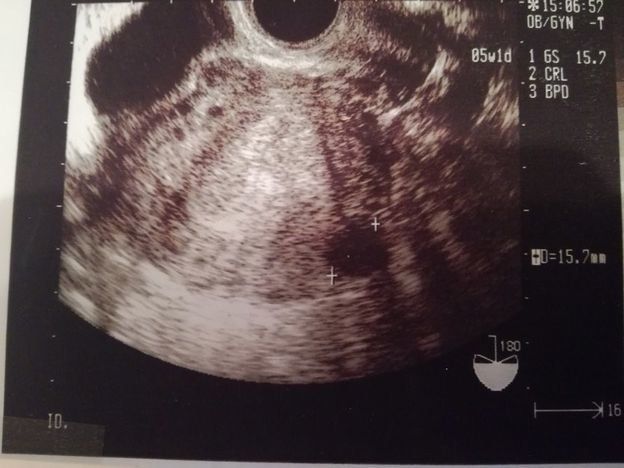

妊娠7週目のエコー写真

画像中央の+と+の間が赤ちゃんで、上の丸い頭のようなものが赤ちゃんに栄養を送る袋(卵黄嚢)だと教えてもらいました。家に帰って、気になっていたエコー写真の記号の意味を調べてみたら以下の通りだと分かり、まだ頭からお尻まで13.4mmなのだとその小ささに驚きました。

GS 胎嚢(たいのう)=胎嚢のサイズ

BPD 児童大横径(じどうだいおうけい)=赤ちゃんの頭の幅。

CRL 頭殿長(とうでんちょう)=赤ちゃんの頭からお尻までの長さ。